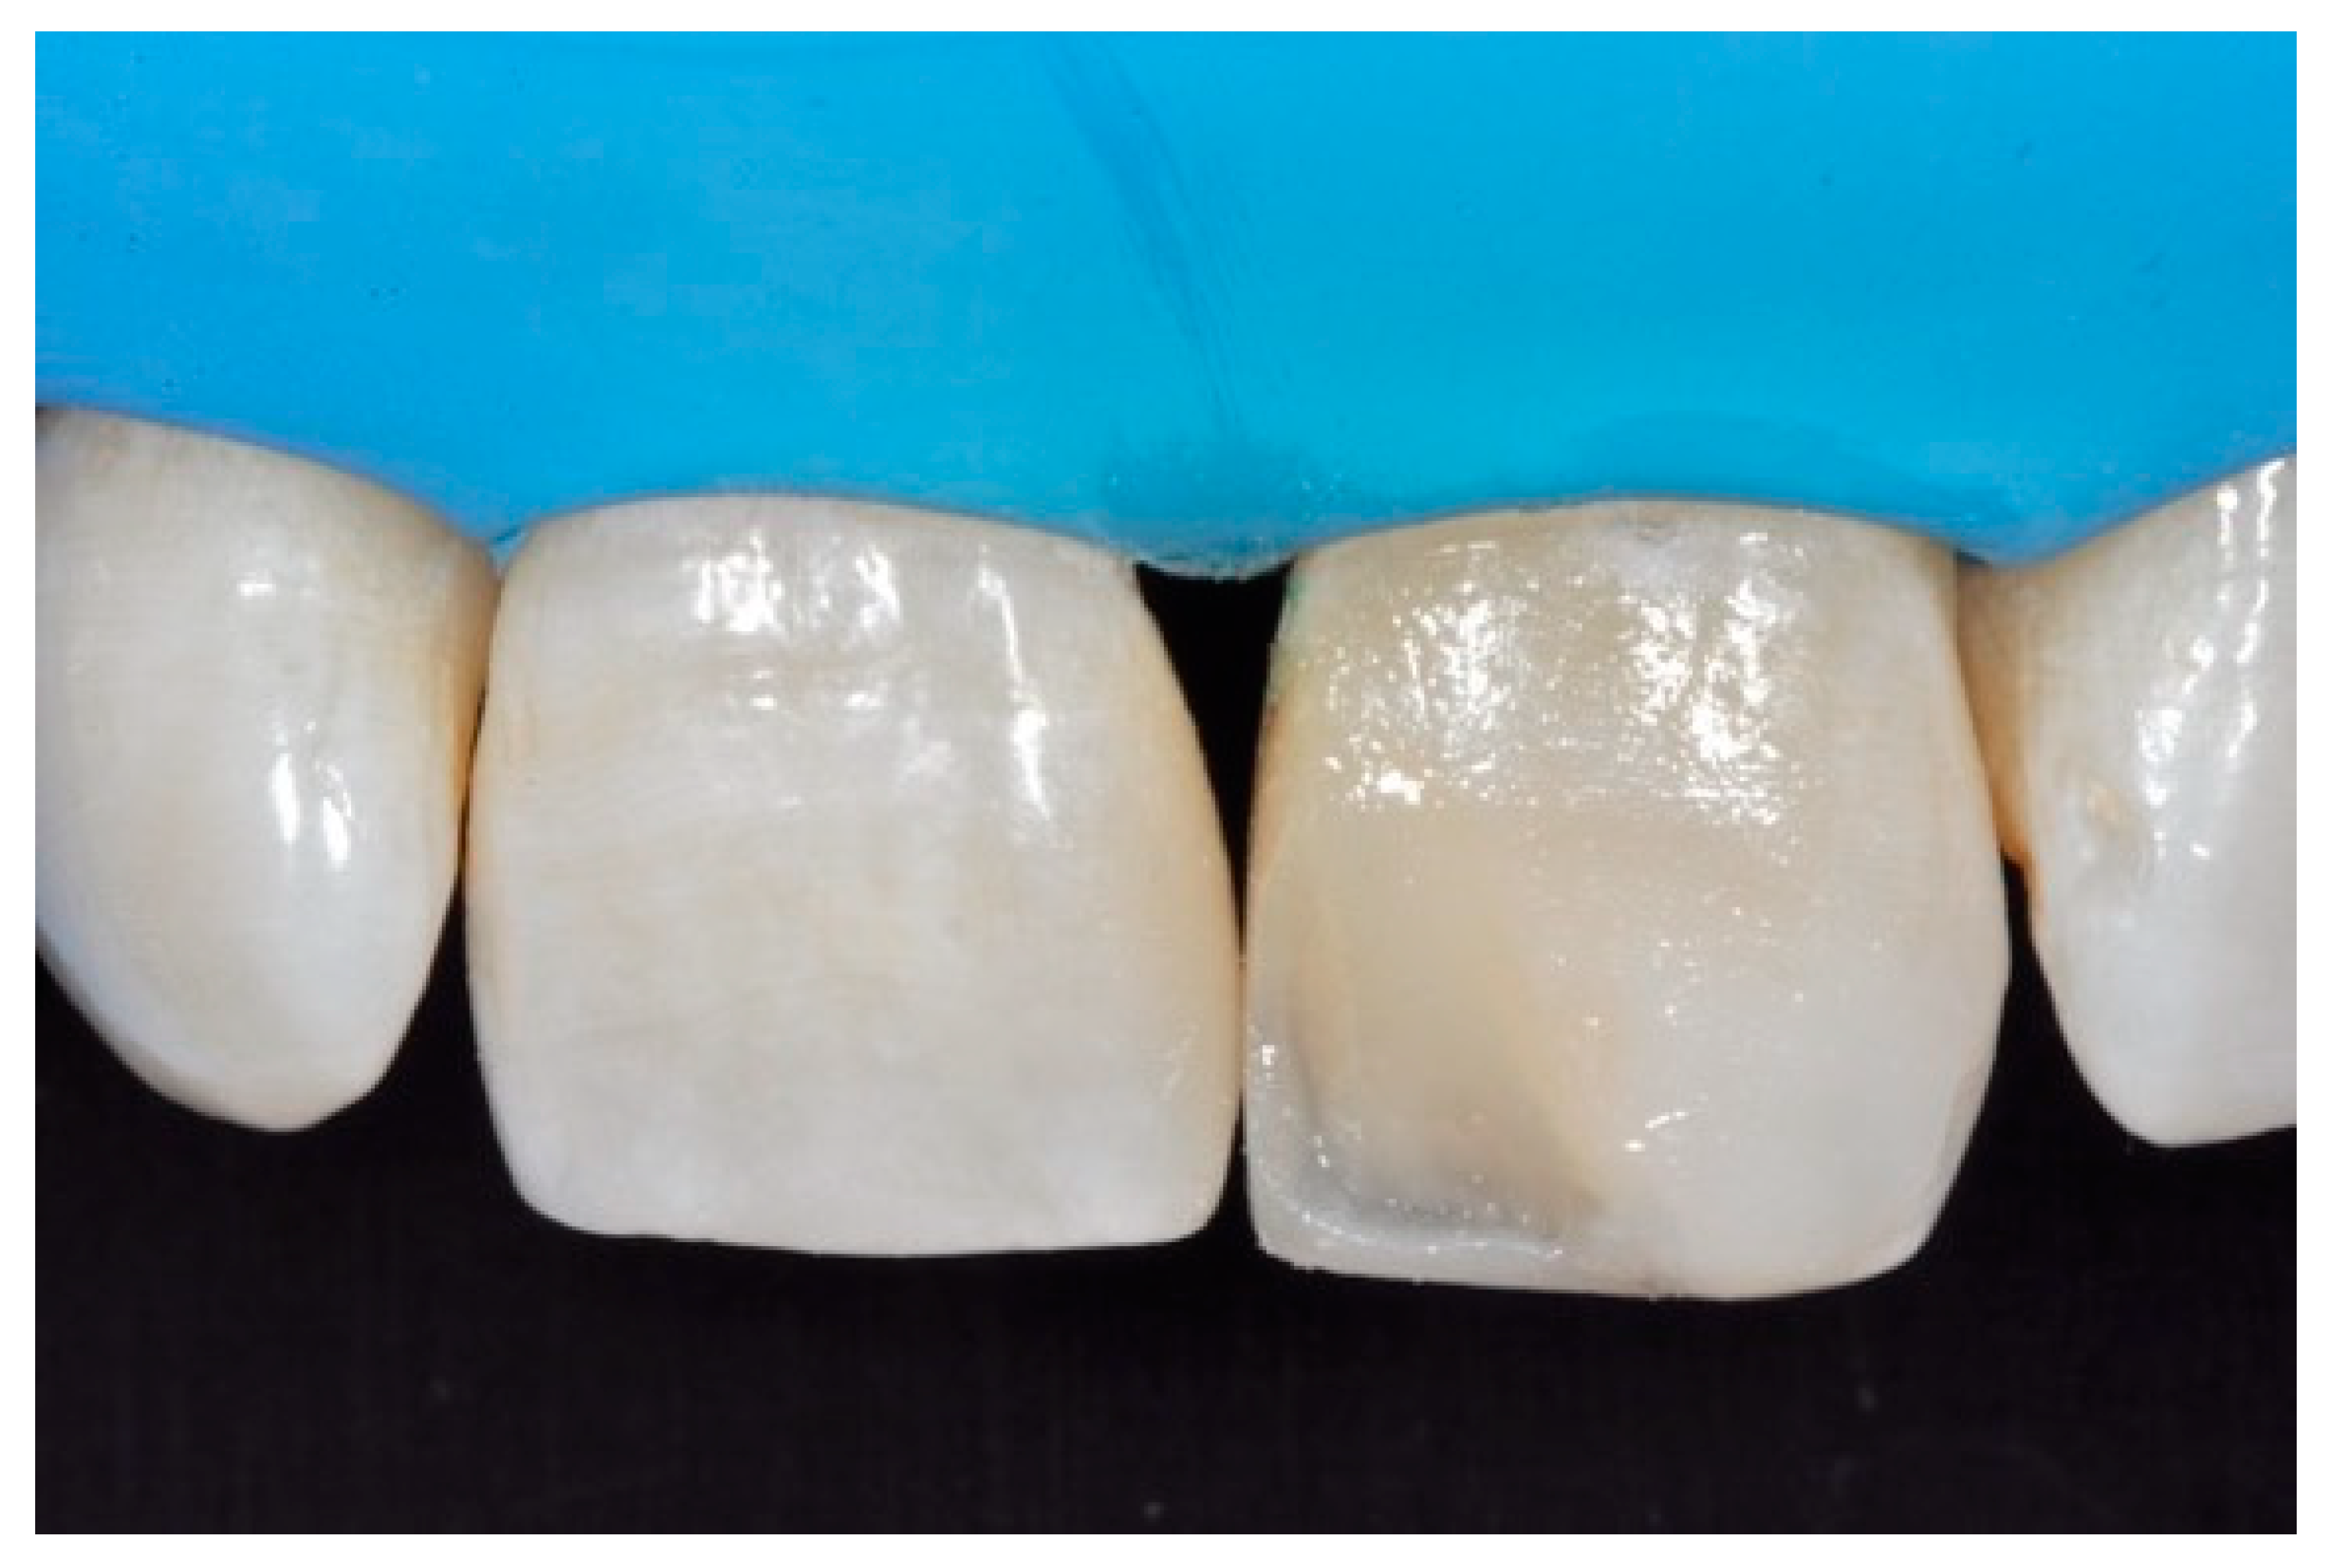

Once completed, the two frames (Clearfil Majesty ES-2, A1E, A2D, Kuraray Noritake Dental, Tokyo, Japan) showed internal and external excesses that were reduced using diamond burs and discs (Figure 33 and Figure 34) strictly following the procedure described in Section 2.1.2 of present article. Excesses were removed from the distal-incisal angle of #2.1 allowing therefore to obtain the desired translucency. After silane application and bonding procedure (Figure 35) as described in Section 2.1.2, restorations were completed (Figure 36 and Figure 37). They both show satisfactory clinical integration 1.5 years post-operative (Figure 38 and Figure 39).

Figure 37.

Final result after finishing and polishing. Reprinted from Restauri diretti nei settori anteriori, G. Paolone, S. Scolavino, © 2021, with permission from Quintessence Publishing Italy.

Figure 38.

At 1.5 years, post-operative clinical view. Reprinted from Restauri diretti nei settori anteriori, G. Paolone, S. Scolavino, © 2021, with permission from Quintessence Publishing Italy.